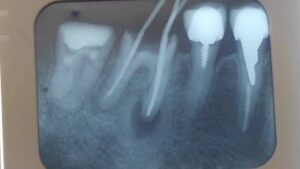

歯の根の先まで薬を詰めて炎症の部分も小さくなっています。